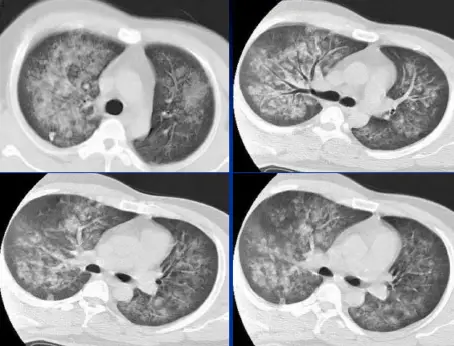

病例:男,33岁,急性肾衰肺水肿。CT表现:①肺间质性肺水肿:两肺血管束增多、增粗,边缘模糊;②肺泡性肺水肿:两肺透光度减低,并见广泛性分布结节样、斑片样密度增高影及毛玻璃样影,边缘模糊,以两肺内、中带分布较明显,形成典型“蝶翼征”;③胸腔积液。